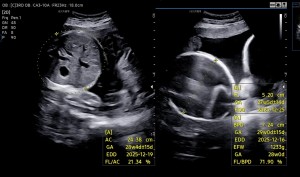

29주차 초음파

쌍둥맘방방

2025-10-01